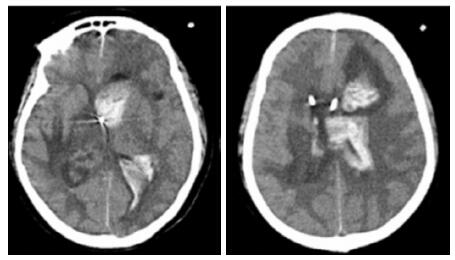

患者,女,54岁,工人,因“头晕5 d”于2019年9月29日至浙江大学附属第二医院急诊就诊。5 d前患者无明显诱因出现头晕,伴行走不稳、四肢乏力,无发热、咳嗽咳痰、胸闷气促、恶心呕吐、四肢抽搐等,未就诊。我院急诊头颅磁共振(MRI)示:右侧丘脑及左侧岛叶异常信号,局部累及右侧中脑(图 1),考虑脑多发占位性疾病。在急诊抢救室予甘露醇100 mL静滴脱水降颅压等对症治疗,5 h后患者逐渐意识模糊。急查血常规:白细胞16.1×109/L,中性粒细胞百分比73.4%;头颅CT示右侧丘脑、左侧岛叶病变,伴脑室扩张(图 2);急诊行“双侧脑室外引流术”,术中引流液呈淡血性。术后诊断:⑴(右侧丘脑)颅内占位性病变,脓肿首先考虑,肿瘤需排除;⑵脑积水;⑶脑疝。患者带气管插管转入ICU进一步治疗。当时体温38.3℃,脉搏99次/min,呼吸频率24次/min,血压169/87 mmHg(1 mmHg= 0.133 kPa),颈软,神志昏迷,右侧瞳孔3 mm,左侧瞳孔2.5 mm,对光反射迟钝。双肺呼吸音粗,可闻及少量啰音。左侧病理征阳性。患者3个月前曾因“反复胸闷气促伴发热1个月余”在本院风湿科住院,当时胸部高分辨CT示两肺间质性肺炎、下叶为著(图 3);血化验示血沉偏高,抗心磷脂抗体阳性;诊断为“间质性肺炎”,住院期间予甲泼尼龙40 mg/d静滴×8 d,60 mg/d静滴×6 d,共住院14 d;出院后予口服甲泼尼龙40 mg/d联合雷公藤多苷片每次20 mg,一日2次治疗;此后规范于本院门诊复诊。本次起病前2个月甲泼尼龙已减量至36 mg/d口服治疗。

| A:右侧丘脑、左侧岛叶病变,伴脑室扩张;B:双侧脑室钻孔引流术后改变,脑室扩张较前(2019-09-29)好转,右侧丘脑、左侧岛叶病变伴出血 图 2 患者2019-09-29头颅CT平扫(A)和2019-09-30头颅CT平扫(B) |

转入ICU后呼吸机辅助通气、甘露醇100 mL/8 h静滴脱水、头孢呋辛1.5 g/12 h静滴抗感染,肠内营养等支持治疗。当晚血常规:白细胞13.3×109/L,中性粒细胞百分比85.3%,C反应蛋白17.1 mg/L,降钙素原0.64 ng/mL。脑室外引流术后次日血化验:白细胞16.6×109/L,中性粒细胞百分比92.8%,C反应蛋白78.4 mg/L;从脑室外引流管留取脑脊液检验:有核细胞6×106/L,红细胞1 960×106/L,蛋白含量1.717 g/L,葡萄糖4.72 mmol/L,细菌培养阴性,涂片未找到细菌;复查头颅CT示:脑室扩张好转,右侧丘脑、左侧岛叶病变伴出血(图 2);胸部CT示,两肺间质性肺炎下叶为著,较前(2019年6月21日)部分好转(图 3)。考虑到炎症指标升高,遂改哌拉西林他唑巴坦3.375 g/12 h静滴抗感染。此后经脑室外引流管反复留取脑脊液送检涂片及培养均阴性。术后第5天行“导航下立体定向颅内病灶活检术+双侧omaya囊置入术”,术中穿刺液呈黄色黏稠脓性,考虑脑脓肿,留取脓液送高通量测序(next-generation sequencing, NGS),并升级为美罗培南2 g/8 h联合利奈唑胺0.6 g/12 h静滴抗感染治疗。术后第7天患者突发血压升高、瞳孔不等大,昏迷程度加深;急查头颅CT示,双侧脑室钻孔引流术后改变,双侧侧脑室引流管走形区出血伴血肿形成;右侧丘脑区积液、积血,双侧脑室积血新发(图 4),甘露醇加量至250 mL/8 h联合地塞米松5 mg/6 h静滴加强脱水;当日术中脓液高通量测序结果回报:皮疽诺卡菌(序列数52 867个)、支气管戈登菌(序列数10个)。确诊脑诺卡菌病,抗菌治疗方案改为亚胺培南西司他丁0.5 g/6 h静滴,联合利奈唑胺0.6 g/12 h和复方磺胺甲恶唑片(0.48 g/片)3片/6 h口服。此后患者仍伴低热,炎症指标呈上升趋势。术后2周患者再次突发血压升高、瞳孔不等大、对光反射消失、神志深昏迷,急查头颅CT示再发脑疝(图 5),急诊行“去骨瓣减压术+脑内血肿清除术”,术后患者仍呈深昏迷状态,双侧瞳孔散大、对光反射消失,次日自动出院。